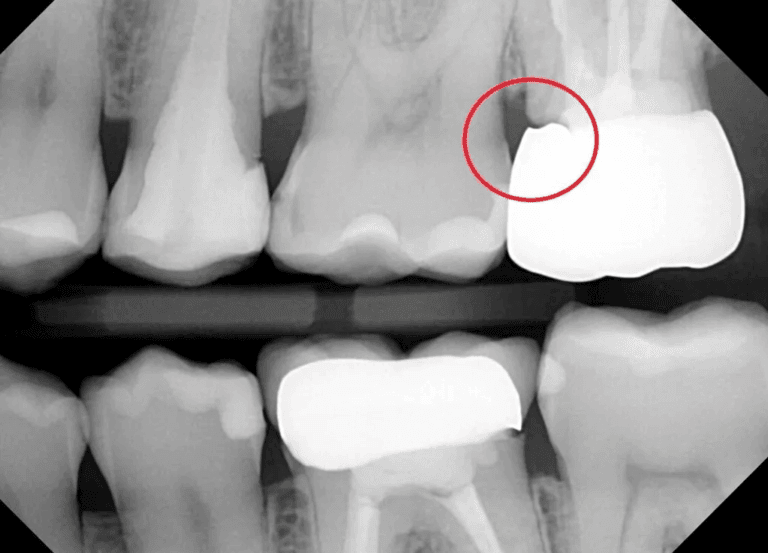

Medir espaços interproximais

Os scanners intraorais podem ter dificuldade em detectar espaços interproximais menores que 0,3 mm devido a limitações na resolução e a presença de saliva.

É importante ter esses espaços mapeados para previnir que a finalização do tratamento tenha diastemas ou que sejam requisitados desgastes interproximais desnecessários.

Recomendamos que esses espaços sejam medidos com um calibrador de espaços e informado na requisição do caso.

existem diastemas entre o 46/45/44 mas o scanner tende a ver tudo como um só.